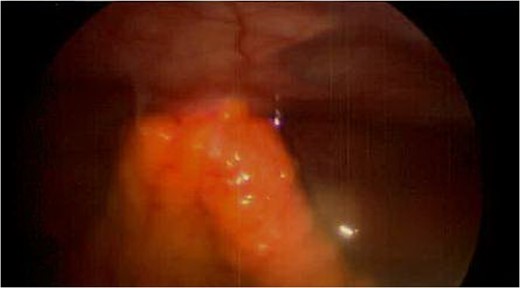

Spigelian hernia. Omental metastatic lesion protruding through the semilunar line.